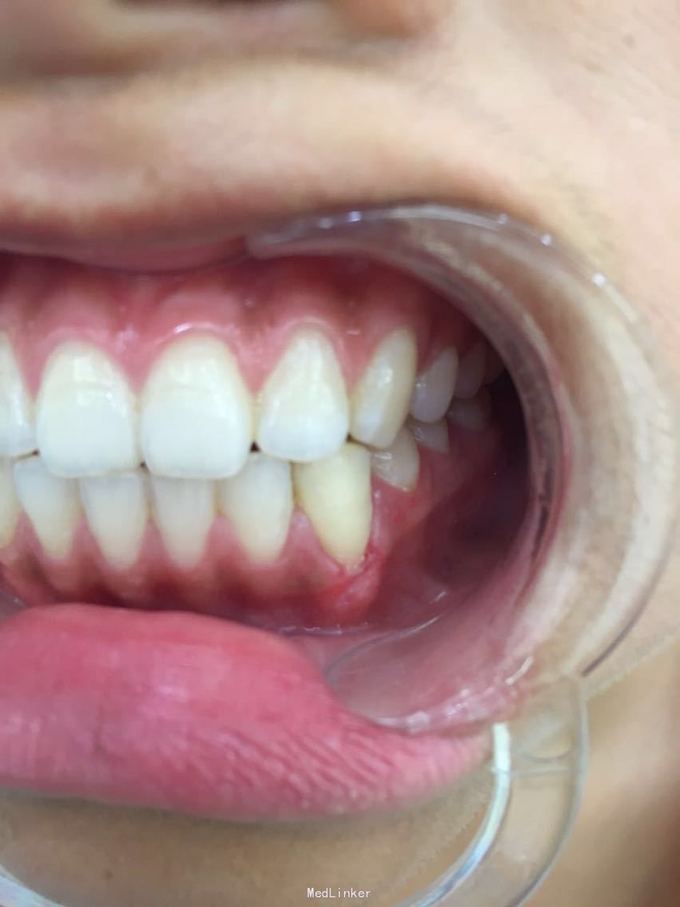

D3牙脱位 D3体外根管治疗后垫底充填,盐水和双氧水浸泡后,刮尽牙根的牙周膜后放置盐水和庆大霉素液中15分钟。局麻下刮除牙槽窝内血凝块至流鲜血后盐水和庆大霉素交替冲洗,明胶海绵拭干牙槽窝,浸泡好的牙体植入牙槽窝内并复位,舌侧树脂牙周夹板固定D123456,牙周上派丽奥。随诊

1天后复诊,3天后复诊,7天后复诊,一个月后复诊,3个月后复诊。1个半月后复诊未发现牙周有较大吸收和炎症感染。